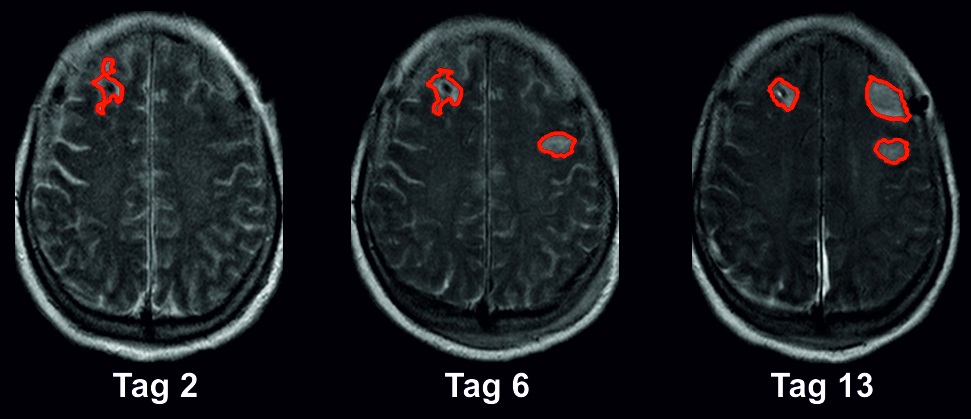

Vorhersage von Hirninfarkten bei komatösen Patienten20. April 2022 Bild: ©pict rider – stock.adobe.com Die Subarachnoidalblutung kann Tage später zu einem ischämischen Schlaganfall führen. Forschende der Charité – Universitätsmedizin Berlin haben jetzt gezeigt, dass massive elektrochemische Wellen im Gehirn einen Schlaganfall in einer solchen Situation ankündigen. Durch die elektrodiagnostische Überwachung dieser Wellen können Hirninfarkte demnach rechtzeitig erkannt werden – insbesondere bei Patientinnen und Patienten, die aufgrund der Blutung intensivmedizinisch behandelt werden und im Koma liegen. Die Erkenntnisse könnten die Basis für neue Therapien legen und wurden jetzt in der Fachzeitschrift „Brain“ veröffentlicht. Elektrodiagnostische Überwachung bei Komatösen Die Subarachnoidalblutung ist eine Form der Hirnblutung, bei der sich das Blut großflächig zwischen die das Hirn umgebenden Häute ausbreitet. Diese Form des hämorrhagischen Schlaganfalls ist ein neurologischer Notfall, weshalb Betroffene umgehend intensivmedizinisch behandelt werden müssen. Subarachnoidalblutungen können wiederum zu ischämischen Schlaganfällen führen. Mehr als die Hälfte der Patientinnen und Patienten mit schwerer Subarachnoidalblutung entwickelt innerhalb der ersten zwei Wochen nach der Blutung einen solchen Schlaganfall. Wissenschaftlerinnen und Wissenschaftler der Charité haben jetzt einen Biomarker identifiziert, der ein hohes Risiko für einen drohenden Schlaganfall nach einer Subarachnoidalblutung anzeigt. „Gerade bei Personen, die im Koma liegen und keine Auskunft über ihren Zustand geben können, ist es schwer zu beurteilen, wann sich ein neuer Hirninfarkt entwickeln könnte“, erläutert Prof. Jens Dreier vom Centrum für Schlaganfallforschung an der Charité und Erstautor der Publikation. „In unserer Studie zeigen wir, dass eine elektrodiagnostische Überwachung diesen Zeitpunkt sichtbar macht. So kann die Therapie auch bei komatösen Patientinnen und Patienten rechtzeitig eingeleitet werden, bevor es zu spät ist.“ MRT-Aufnahmen nach Subarachnoidalblutung. Bild: ©Charité/Jens Dreier Identifikation von Spreading Depolarizations Gemeinsam mit seinem Team hat Dreier den Biomarker auf Basis der sogenannten Spreading Depolarizations entdeckt. Das sind massive elektrochemische Entladungswellen, die durch die giftigen Blutabbauprodukte der Hirnblutung hervorgerufen werden. Die davon betroffenen Hirnareale benötigen dann sehr viel Energie, um wieder in den Normalzustand zurückzukehren. In einem gesunden Gehirn sind sehr kurze Depolarisationen von Nervenzellen normal und mit der Blutversorgung gekoppelt. Das heißt, dass das Gehirn die Gefäße entsprechend weit stellen und einen erhöhten Energiebedarf mit vermehrtem Blutfluss ausgleichen kann. Treten die massiven, langdauernden und krankhaften Spreading Depolarizations jedoch nach einer Subarachnoidalblutung auf, können zusätzlich Signalkaskaden zwischen Nervenzellen und Blutgefäßen gestört sein, so dass die Nervenzellentladung eine extreme Verengung der Gefäße auslöst. In der Folge fehlt den Nervenzellen die Energie, um sich wieder aufzuladen. Verbleiben sie zu lange in diesem entladenen Zustand, beginnen sie irgendwann abzusterben. „Eine wissenschaftliche Erkenntnis der vergangenen Jahre ist jedoch zentral“, betont Dreier: „Die Entladungswelle ist bis zu einem gewissen Grad reversibel. Das bedeutet also, dass sich die Nervenzellen auch wieder erholen können, wenn das Nervengewebe rechtzeitig durchblutet und so mit Sauerstoff versorgt wird.“ Elektrodenimplantation unter die harte Hirnhaut Hier setzt die vorliegende klinische Studie an, die an fünf verschiedenen Universitätskliniken durchgeführt wurde. Um die Spreading Depolarizations präzise zu messen, nutzten die Forschenden die Elektrokortikographie, ein Verfahren der modernen Neurointensivmedizin zur elektrodiagnostischen Überwachung der Gehirnströme. Dafür wurden den Betroffenen mit Subarachnoidalblutung bei Klinikeinweisung Elektroden unter die harte Hirnhaut implantiert. Zusätzlich verwendeten die Wissenschaftlerinnen und Wissenschaftler bildgebende Methoden wie Magnetresonanztomografie (MRT) und Computertomografie (CT). Sie werteten insgesamt rund 1000 Bilder des Gehirns von 180 Patientinnen und Patienten mit Subarachnoidalblutung aus. Verlust von Hirngewebe könnte verhindert werden In dieser bislang größten klinischen Studie zu Spreading Depolarizations konnten sie feststellen, dass durchschnittlich 46 ml Hirngewebe in der Frühphase verloren gehen, also bereits, wenn die Betroffenen in die Klinik kommen. Weitere durchschnittlich 36 ml werden in den ersten zwei Wochen beschädigt, während sich die Patientin oder der Patient in intensivmedizinischer Behandlung befindet. „Diese 36 Milliliter Hirngewebe könnten im Prinzip gerettet werden“, erklärt Dreier. „Wir können die Entstehung der Hirninfarkte elektrodiagnostisch in einem Stadium nachweisen, in dem die Veränderungen noch reversibel und modifizierbar sind. Die Beobachtung der Spreading Depolarizations kann demnach als Biomarker in Echtzeit genutzt werden. Sie ersetzt gewissermaßen den Austausch mit den Patientinnen und Patienten, die ihre Einschränkungen und Leiden nicht äußern können, da sie bewusstlos sind. So können wir diejenigen identifizieren, denen ein weiterer Schlaganfall droht und frühzeitig geeignete Therapiemaßnahmen einleiten. Personen, bei denen sich kein weiterer Hirninfarkt ankündigt, erhalten dagegen keine zusätzlichen Medikamente. Potenzielle Nebenwirkungen können auf diese Weise vermieden werden.“ Kopplung mit Künstlicher Intelligenz Dieses Vorgehen entspricht dem Ansatz der Präzisionsmedizin, bei der die Therapie gezielt auf das Individuum zugeschnitten wird. Die Forschenden möchten das Monitoring der Spreading Depolarizations zukünftig weiter als Frühwarnsystem erproben und idealerweise im Klinikalltag etablieren, um die Behandlungsoptionen bei Schlaganfällen stetig zu verbessern. Dabei werden Verfahren künstlicher Intelligenz eine große Rolle spielen, um die elektrodiagnostischen Daten automatisiert zu analysieren und so intensivmedizinisches Personal in Echtzeit zu alarmieren, wenn das Hirngewebe der bewusstlosen Patientin oder des bewusstlosen Patienten in eine bedrohliche Lage gerät.